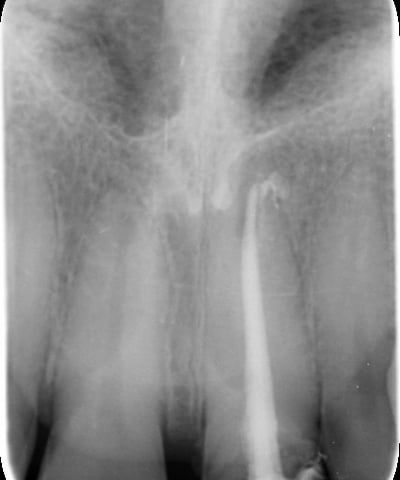

Perno moncone inadeguato: la mancanza di stabilità del perno esistente causava la continua decementazione della corona, rendendo necessario un intervento risolutivo.

Moncone non ritentivo

2. Sostituzione del Perno Moncone

Il perno moncone preesistente è stato rimosso e sostituito con un perno in fibra di vetro. Questo materiale offre vantaggi significativi:

Elasticità simile alla dentina naturale, riducendo il rischio di fratture radicolari.

Elevata adesione ai materiali compositi, garantendo una maggiore stabilità della ricostruzione.

Radiotrasparenza, permettendo un migliore controllo radiografico nel tempo.